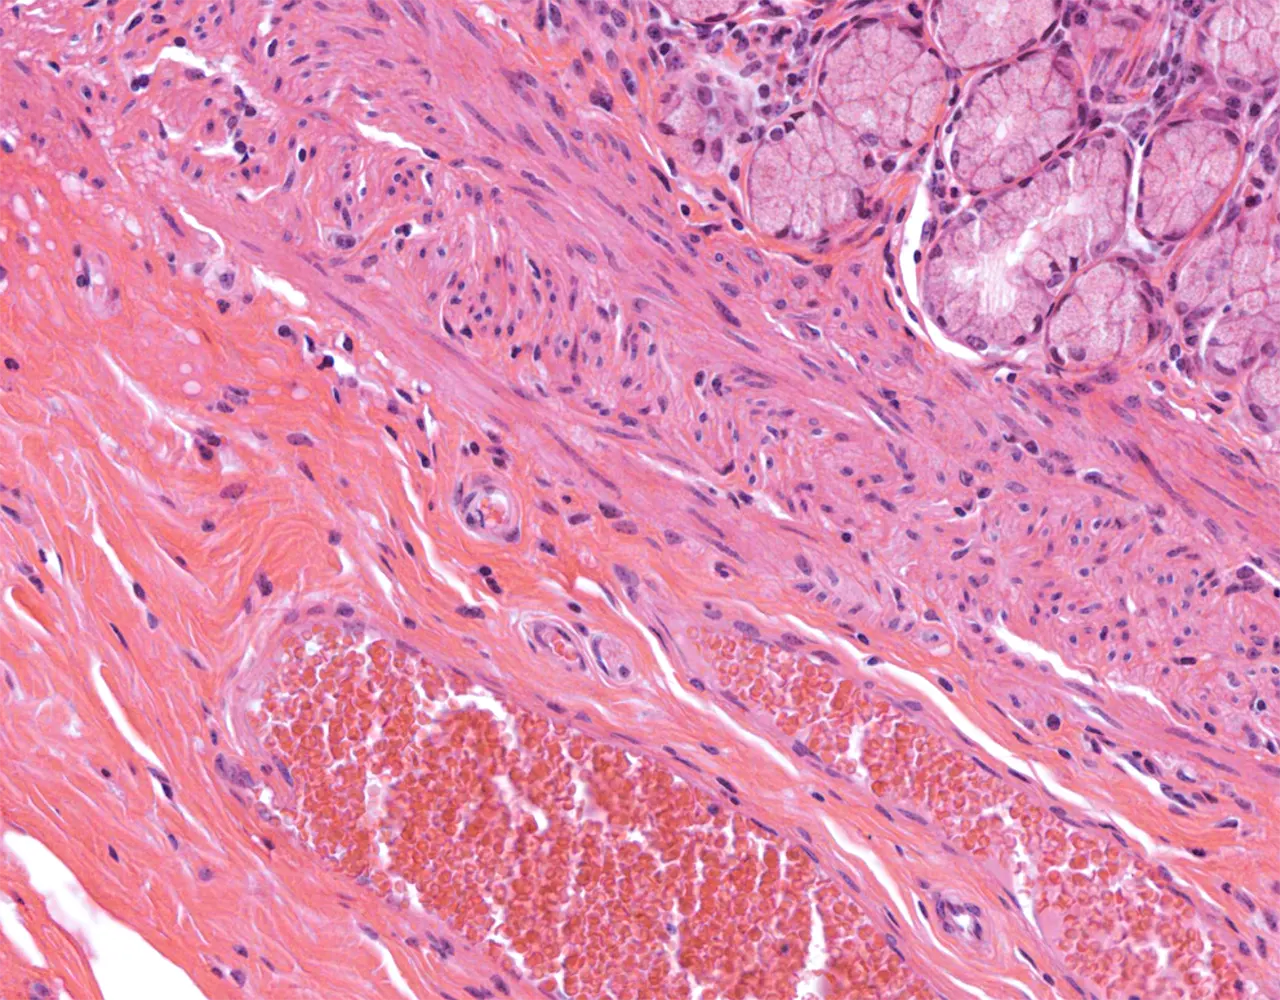

- The wall of the stomach is composed of four layers, from the innermost to the outermost: mucosa, submucosa, muscularis propria, and serosa.